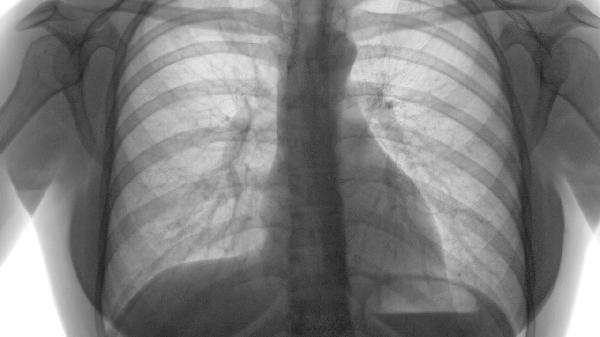

治疗肺气肿可遵医嘱使用补肺活血胶囊、蛤蚧定喘胶囊、金水宝胶囊、百令胶囊、固本咳喘片等中成药。肺气肿属于慢性阻塞性肺疾病范畴,中药治疗需结合辨证分型,建议在医生指导下规范用药。

肺气肿患者除规范用药外,需严格戒烟并避免二手烟暴露,坚持腹式呼吸训练改善肺功能。冬季注意防寒保暖,预防呼吸道感染。饮食宜清淡富含优质蛋白,如鱼肉、蛋类等,适量食用梨、白萝卜等润肺食材。定期复查胸部CT和肺功能,若出现咯血、下肢水肿等症状需立即就医。中药治疗需持续3-6个月方能显效,不可自行增减药量。